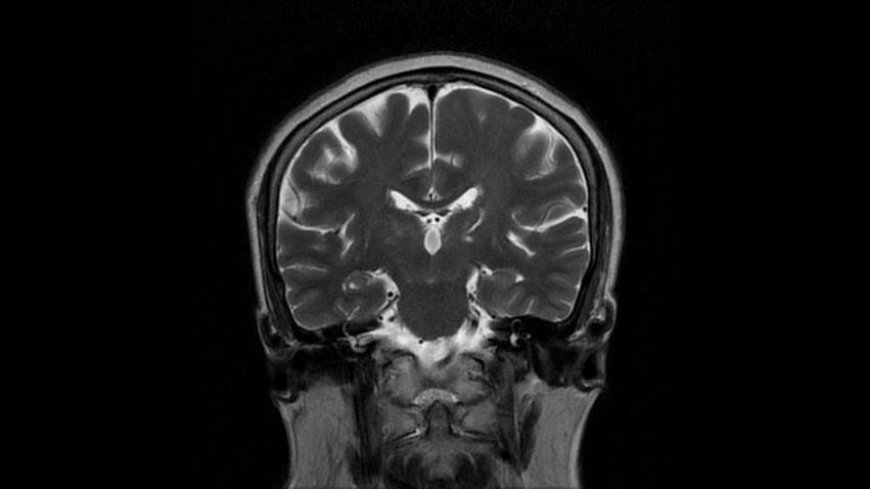

MRI of Brain

Coronal T2